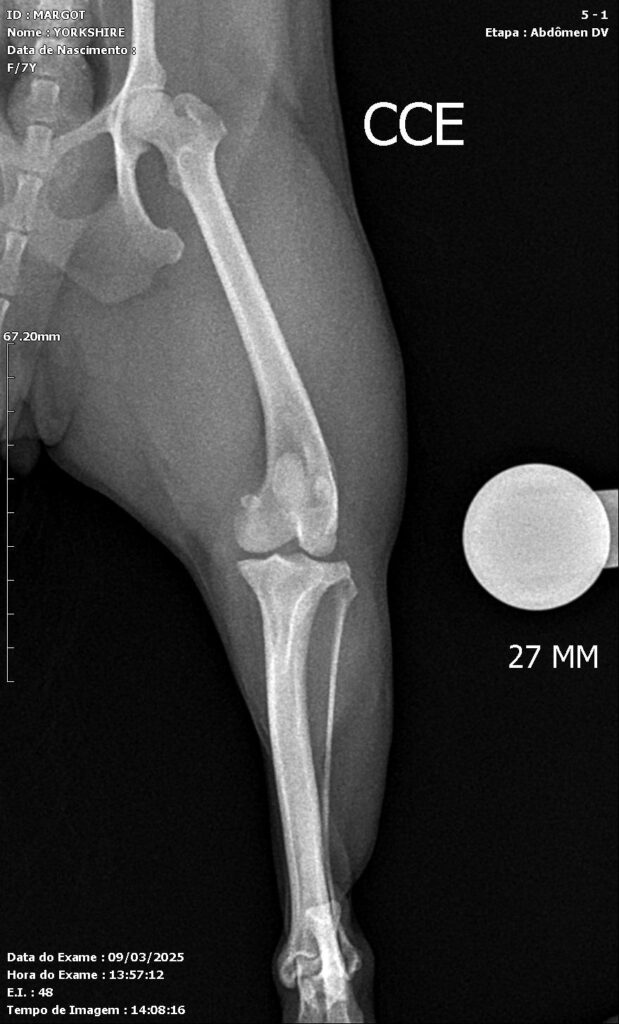

On orthopedic examination, cranial drawer and tibial compression tests were positive. Patellar instability testing revealed a grade II patellar luxation. Radiographic evaluation demonstrated narrowing of the femorotibial joint space, incongruence of the femoropatellar joint, caudal displacement of the left patella on the mediolateral view, and medial displacement on the craniocaudal view. Additionally, a pronounced cranial deviation of the tibial plateau relative to the femoral condyles was observed. Based on these clinical and radiographic findings, a diagnosis of patellar luxation associated with joint effusion and cranial cruciate ligament insufficiency was established (Figures 1 and 2).

Figures 1 and 2: Preoperative radiographs of the right pelvic limb of a 7-year-old female Yorkshire Terrier. (A) Mediolateral projection showing medial patellar luxation (MPL) associated with cranial cruciate ligament disease. (B) Craniocaudal projection demonstrating misalignment and joint alterations consistent with the described orthopedic conditions.